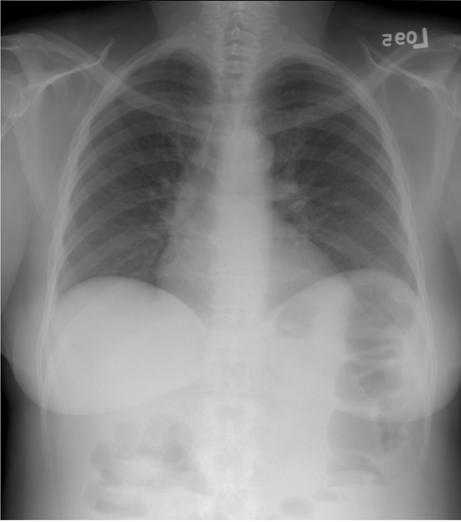

Figure 4a. A digital radiograph of the chest taken with a general purpose CR screen (GP screen, Eastman Kodak Company) is illustrated using no display processing. To display the wide range of raw image values, a wide latitude grayscale rendition has been used that results in poor tissue contrast.

Figure 4b. An unsharp mask image derived from the chest image in figure 4a is illustrated with the grayscale reversed.

Figure 4c. The chest image in figure 4a is illustrated with contrast enhancement based on the unsharp mask of figure 4b. The unsharp mask values are used to adjust the raw image values so that the image may be displayed with a narrow latitude grayscale rendition resulting in improved tissue contrast. An equivalent photographic process would use the unsharp mask as illustrated to illuminate the orginal radiograph and make a high contrast copy.